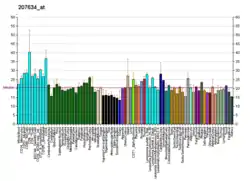

- "Figure 1 - available via license: Creative Commons Attribution 3.0 Unported" - ↑ Wang X, Teng F, Kong L, Yu J (August 2016). "PD-L1 expression in human cancers and its association with clinical outcomes". OncoTargets and Therapy. 9: 5023–39. doi:10.2147/OTT.S105862. PMC 4990391. PMID 27574444.